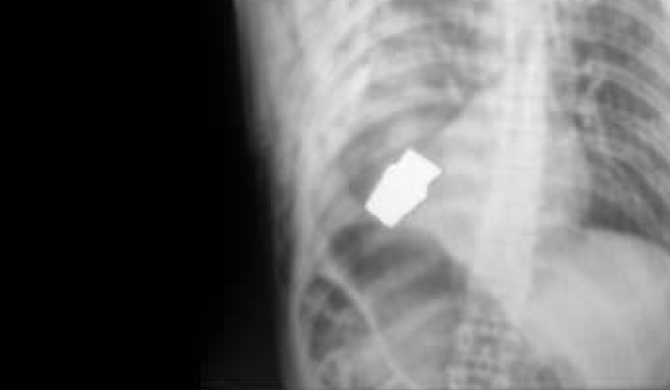

A wounded soldier was brought to a Ukrainian front-line hospital in early January. The wound was very close to his heart, and his condition was serious. However, the seriousness of this wound became clear only after X-rays. The soldier had an unexploded grenade launcher shell in his body. This required an urgent operation. Such a situation threatened the life of both the patient and the doctor. But there was no other way out.